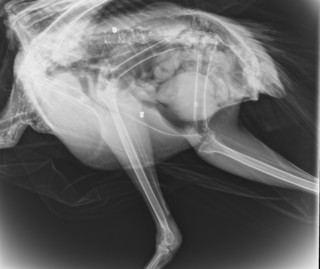

Ο σύλλογος ΑΝΙΜΑ έκανε ανάρτηση στο Facebook, δημοσιεύοντας φωτογραφίες με το τραυματισμένο ζώο και από τις ακτινογραφίες του, ενώ έγραψε το εξής:

«Ένα παγώνι από τον αρχαιολογικό χώρο της Κνωσού στάλθηκε μέσω του Μουσείου Φυσικής Ιστορίας Κρήτης, επειδή κούτσαινε εδώ και λίγο καιρό.

Με έκπληξή μας, εμφανίζοντας την ακτινογραφία, είδαμε δυο βολίδες αεροβόλου κι ένα σκάγι μέσα στο σώμα του!

Το ζώο αυτό έχει πυροβοληθεί τρείς φορές, την ίδια ώρα ή διαφορετικές δεν μπορούμε να ξέρουμε, ούτε αν ο δράστης είναι ένας ή δύο ή τρεις, μέσα ή δίπλα σε έναν από τους πιο πολυσύχναστους αρχαιολογικούς χώρους της Κρήτης και της Ελλάδας γενικότερα».

Ακολουθούν φωτογραφίες: